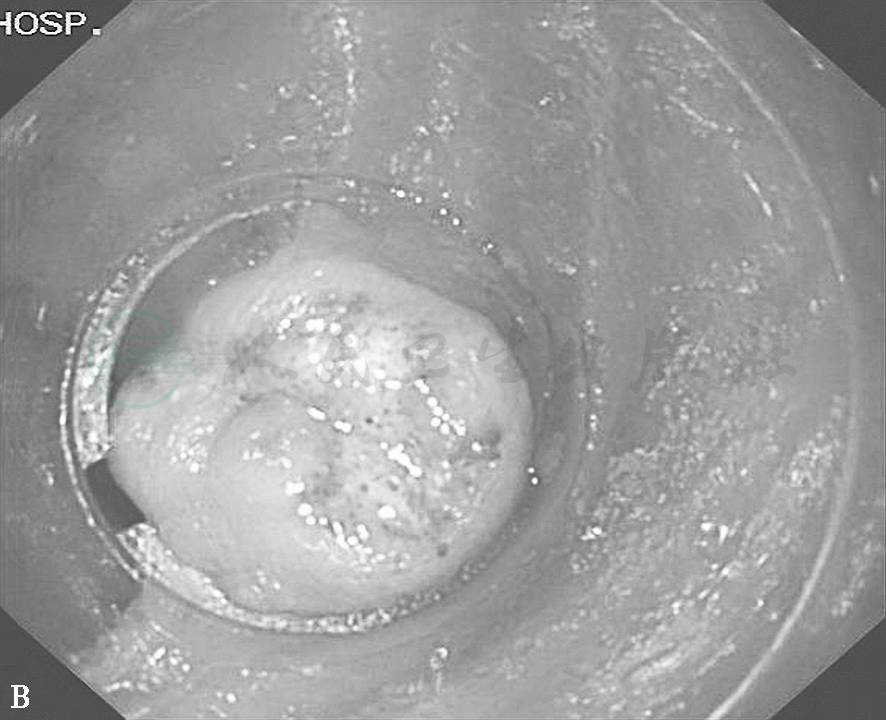

气囊辅助式小肠镜(BAE)包括双气囊小肠镜(DBE)和单气囊小肠镜(SBE),二者均可完成全小肠的直视检查,而且可在病变部位进行活检、黏膜染色、息肉摘除等操作,必要时结合内镜下超声等辅助手段,可进一步明确小肠肿瘤的性质,是一种安全、直观、可靠的检查手段,是诊断小肠黏膜和黏膜下层肿瘤的最理想方法。小肠镜可以直接诊断小肠息肉、静脉瘤、平滑肌瘤等病变(见图6)。

图6 小肠良性肿瘤的小肠镜表现

A.空肠巨大息肉;B.小肠带蒂息肉;C.回肠静脉瘤;D.空肠平滑肌瘤